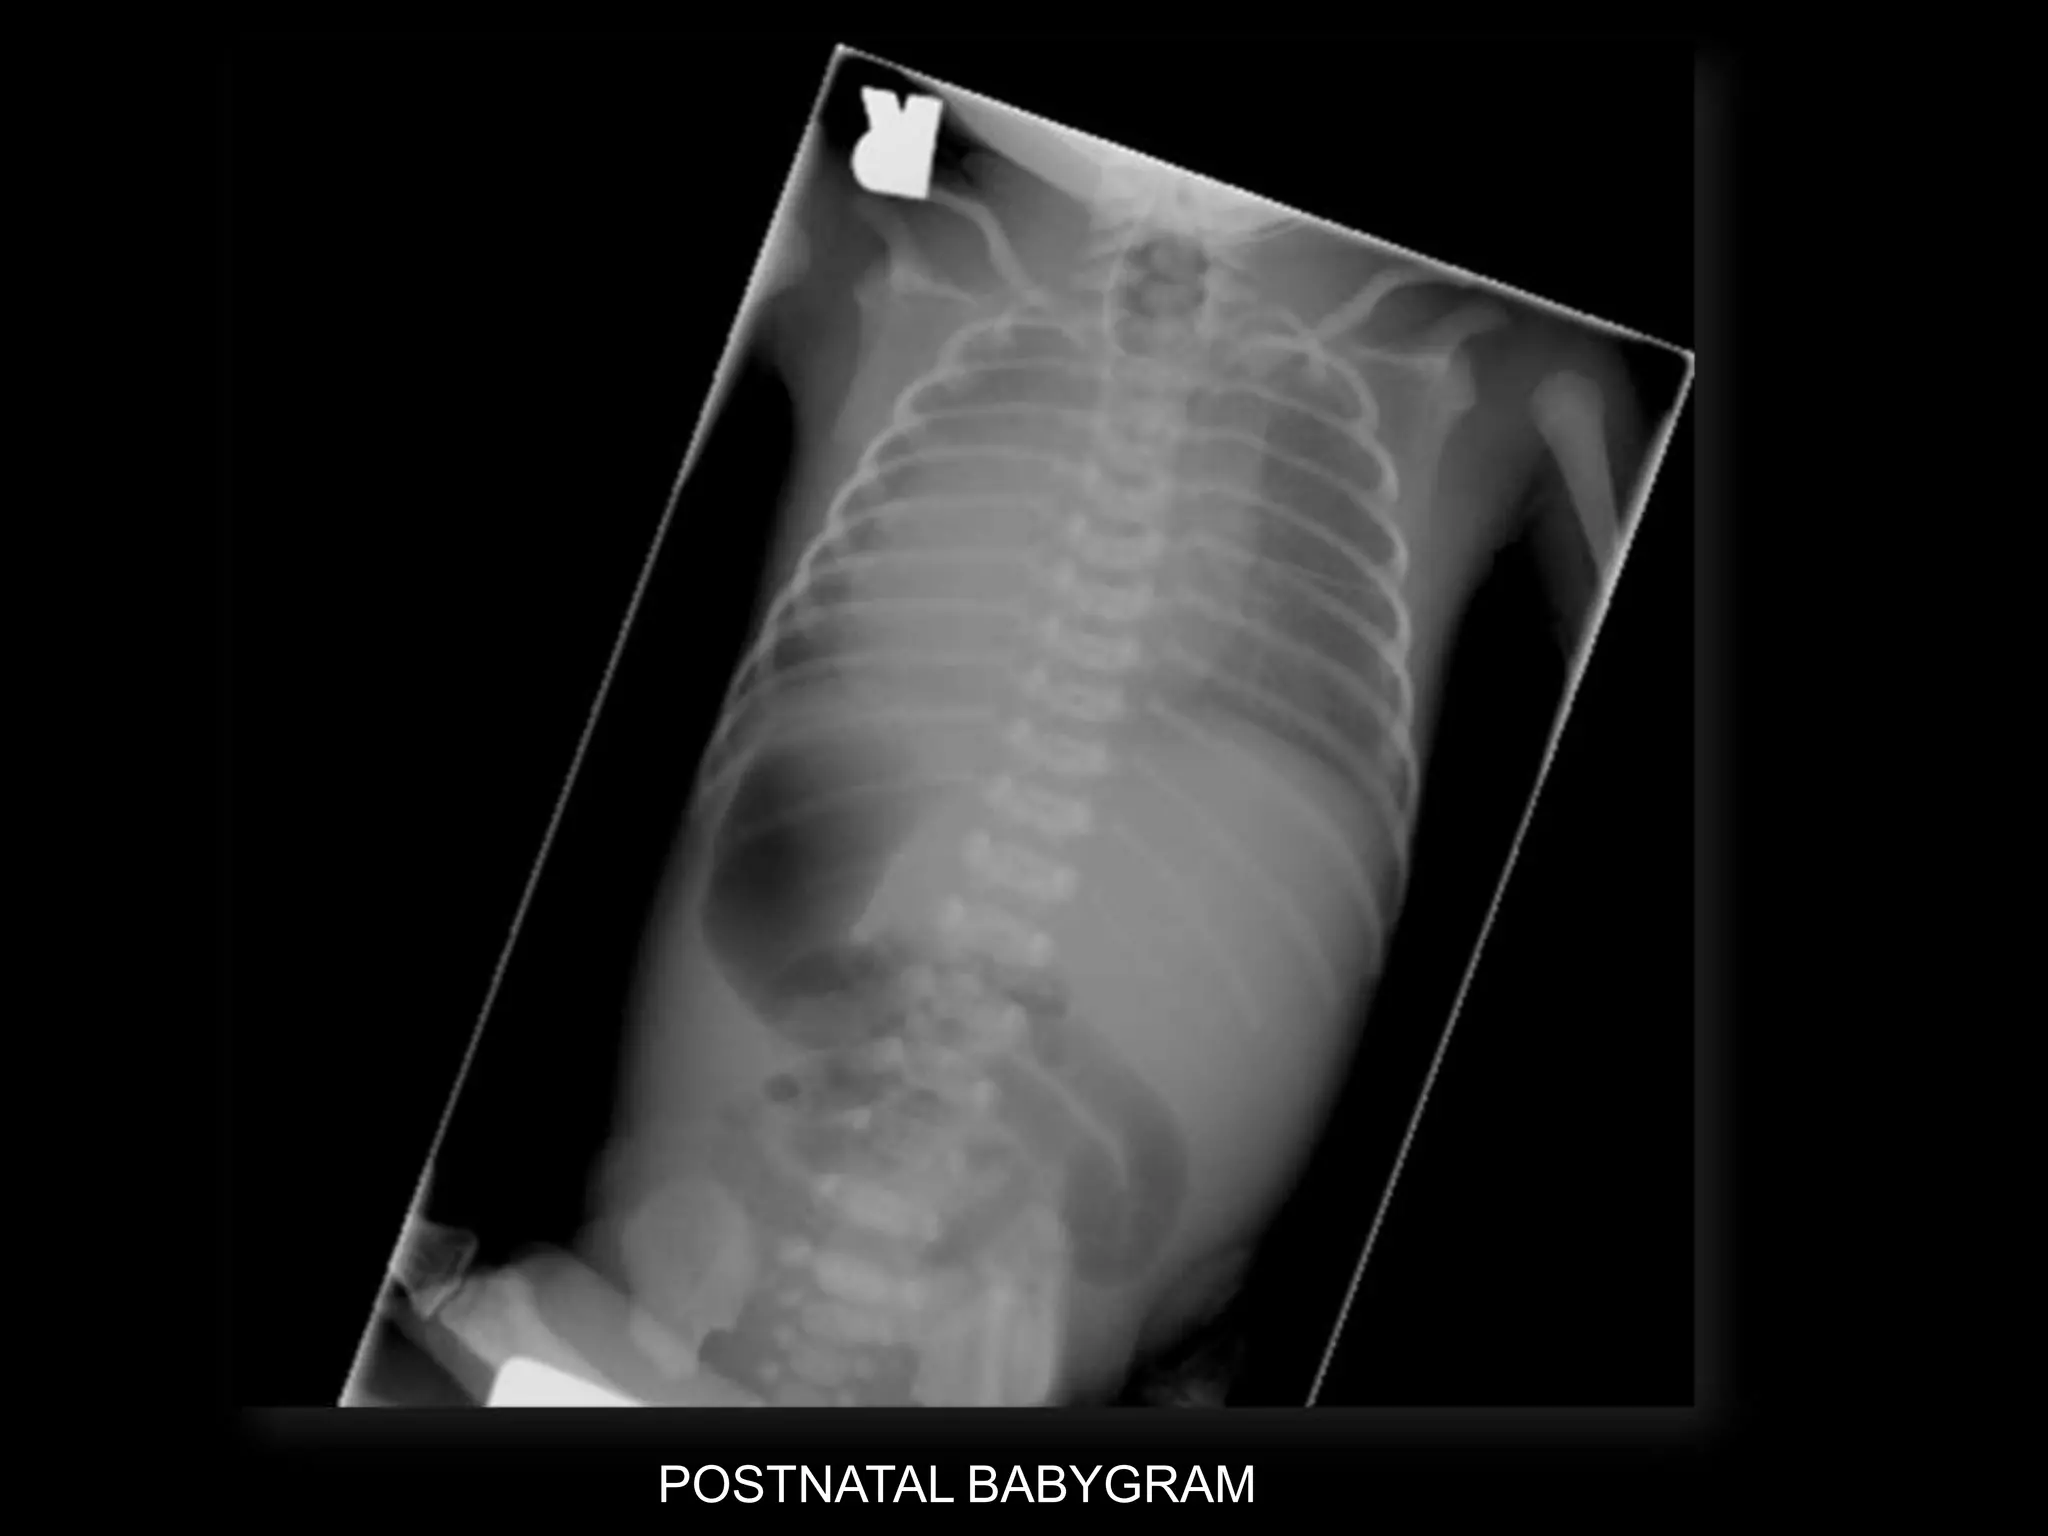

POSTNATAL BABYGRAM

-Cephalic

-Heart - right side

-Stomach โ€“ right side

-Liver โ€“ left side

-Des colon โ€“ right side

Situs Inversus Totalis

โ€ข 3-5% with cardiac abnormalities

โ€ข 25% with primary ciliary dyskinesia (PCD)

โ€“ Kartagenerโ€Ÿs Syndrome

โ€“ Chronic sinus infections; respiratory infections;

infertility

-Cephalic -Heart - rightside -Stomach โ€“ right side -Liver โ€“ left side -Des colon โ€“ right side